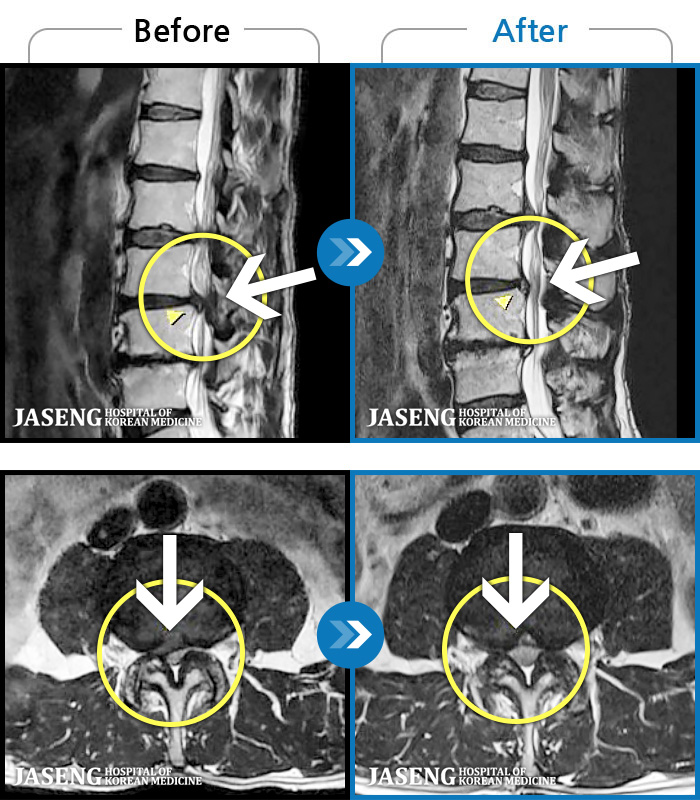

- MRI ġ

97 MRI ũ ʸ Ȯϼ.